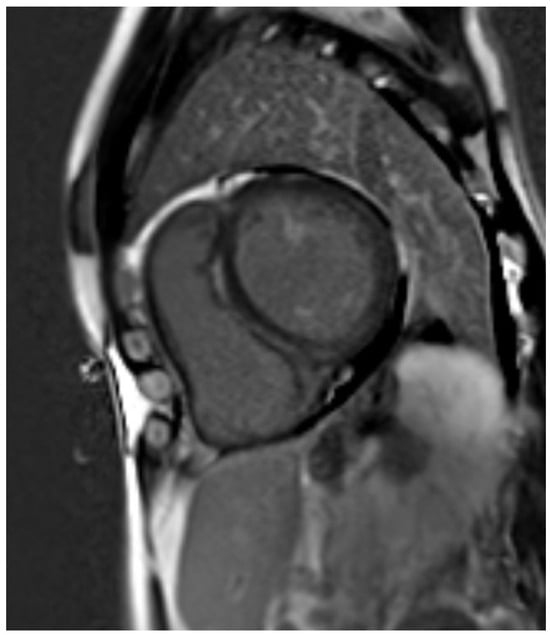

4. CMR Applications in Ischemic Heart Disease